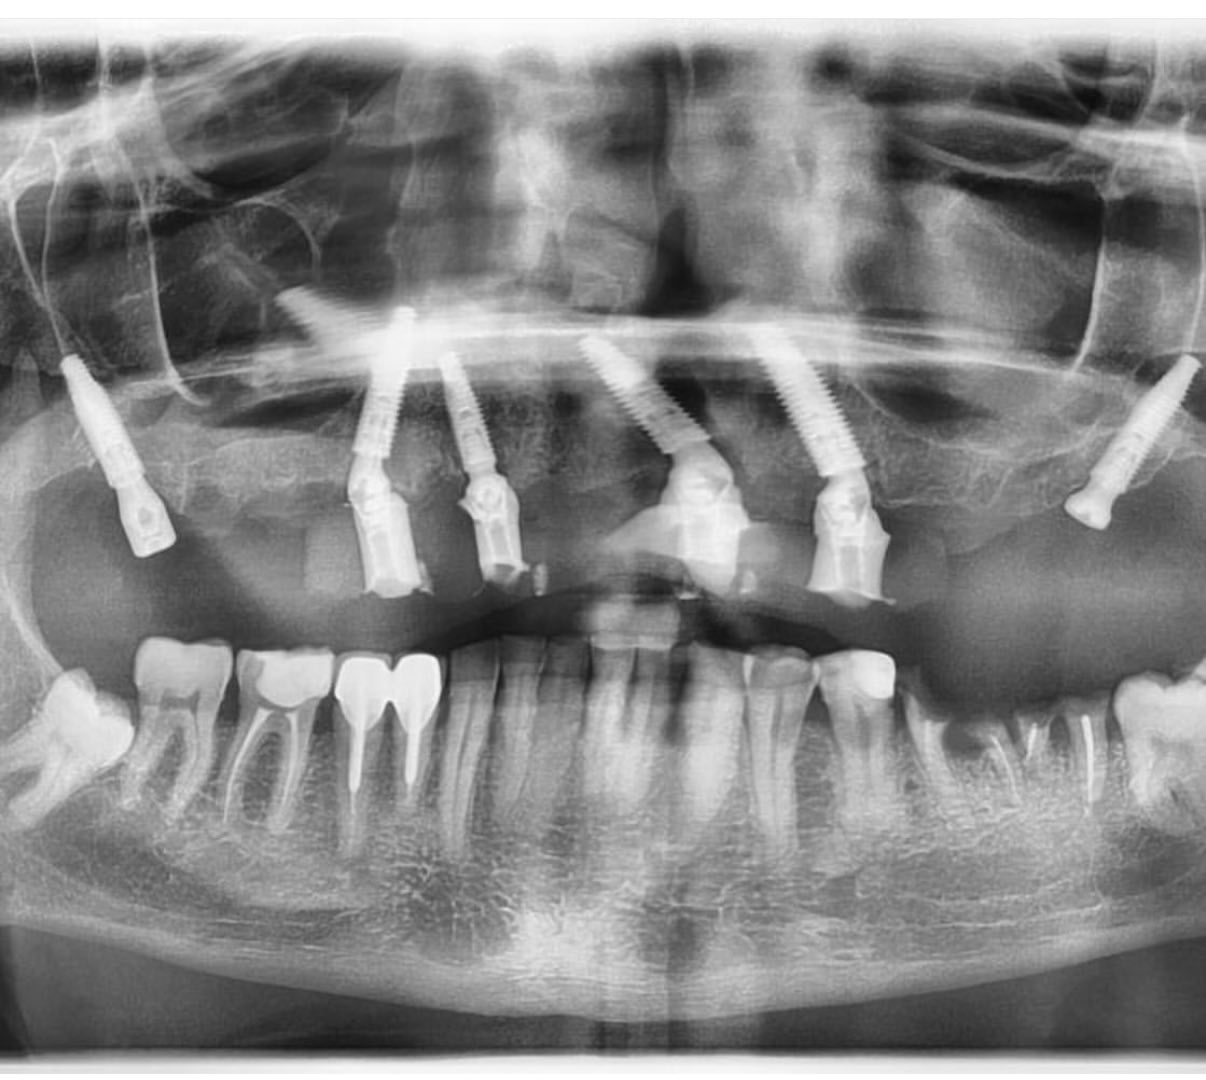

Вживленные импланты можно 114 фото